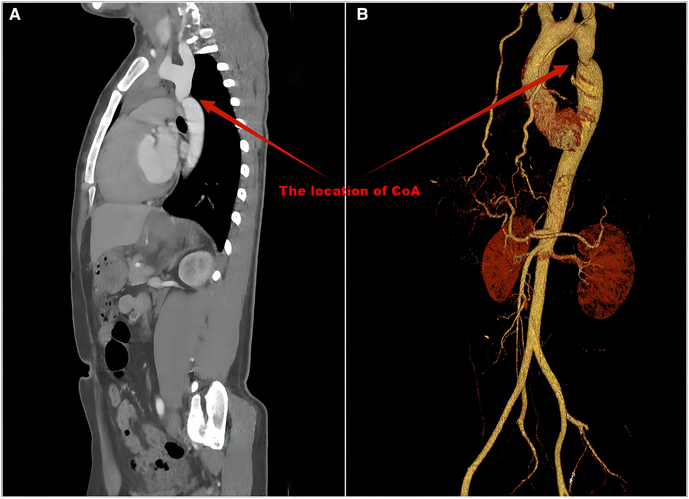

All 48 patients (100%) had BP measurements in upper and lower extremities. Twenty-six of the 48 hypertensive patients received antihypertensive therapy. Three of the 26 patients had normal BP at our institution due to adequate medication. The BP of 47 (97.9%) patients in the upper limb was ≥20 mmHg higher than that in the lower limb, and the BP of 1 patient in the upper limb was greater than 0 and less than 20 mmHg than that in the lower limb. All patients underwent ECHO evaluations, and CoA was detected in 35 (72.9%). CT/MRI was performed in 44 patients and had a CoA detection rate of 100% (Table 2). Seventeen (35.4%) patients underwent cardiac catheterization with a median peak systolic pressure gradient of 34 (range, 20–85) mmHg. CT and 3D reconstruction of CoA are shown in Figure 3. All patients were diagnosed at our institution (Figure 1).

Figure 3

CT (A) and 3D reconstruction (B) of CoA. The precise location, diameter and length of the narrowing can be shown.